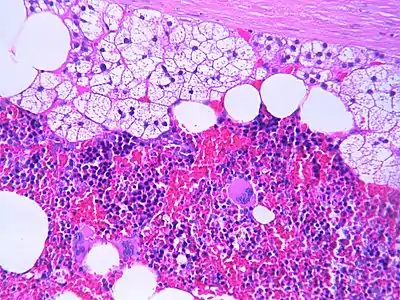

The microscopic view of a myelolipoma shows the presence of normal adrenal cells, fat (adipose) cells, and the three lineages of the myeloid precursors

Microscopic features

The typical microscopic features of myelolipomas are shown in the image. There is a mixture of normal adrenal tissue, fat, and a full trilineage maturation of the three major blood-forming elements: myeloid (white blood cell forming), erythroid (red blood cell forming), and megakaryocytic (platelet forming) lines.[1]